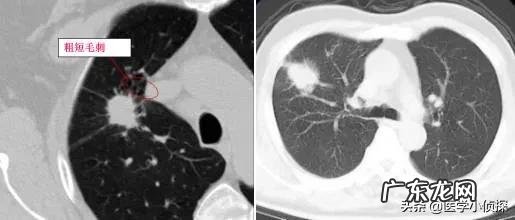

而同样 , 我们既不知道它是个什么东西 , 也不知道它是怎么来的 , 有一部分人可能跟我们的肺部炎症有关;而有一部分可能与肺结核有关 , 但具体一个人为什么会长肺结节 , 目前并没有研究清楚 , 这就导致了很多在看到自己体检报告肺部有结节时候会有点恐慌!